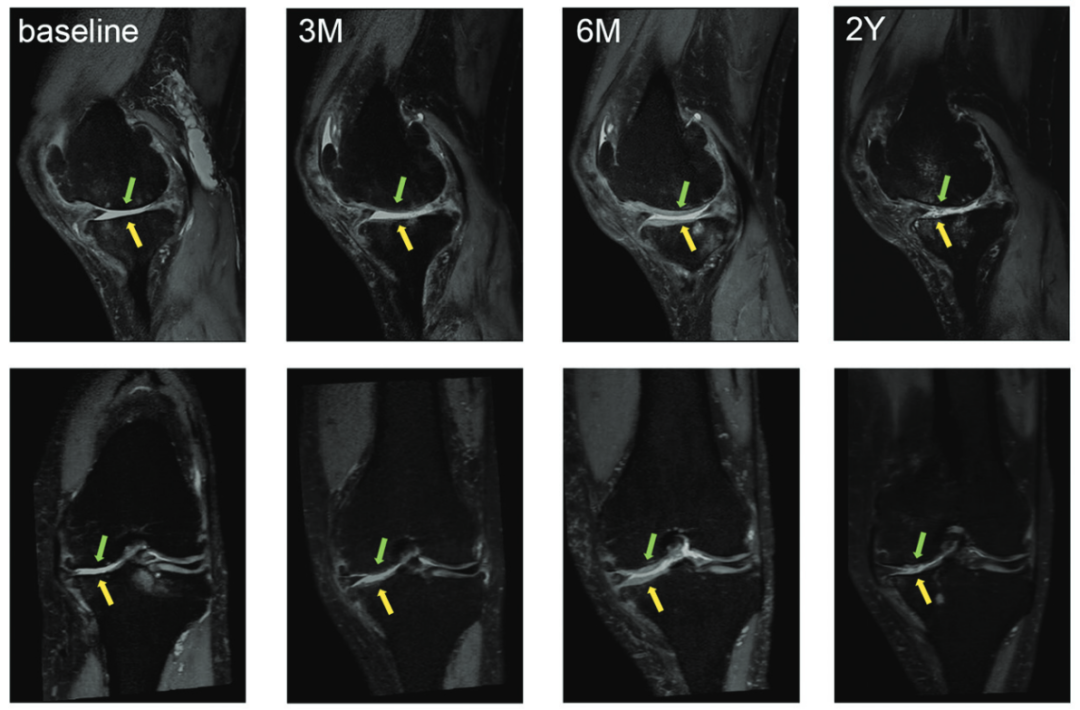

2017年,发表于《美国运动医学杂志》的一项临床研究显示,18名膝关节炎患者,采用关节腔内注射间充质干细胞的治疗方法,显著改善了患者的膝关节功能,关节软骨损伤得到有效修复,患者生活质量大幅提升。随访时间长达两年,经过核磁共振等检查发现,干细胞的临床疗效得到了有效保持。

核磁共振成像(MRI)检查评估